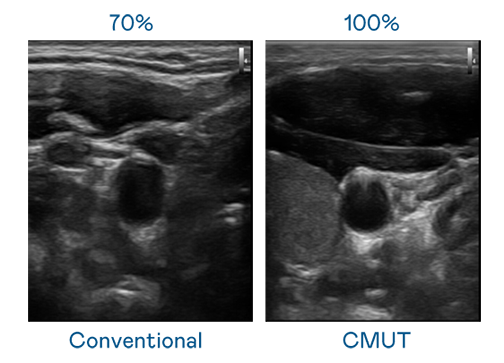

CMUT 技术是一种用电容式微机电元件来产生超音波讯号的技术。与传统 PZT 压电式技术相比,CMUT 频宽增加 30%,更宽频的超音波讯号让影像解析度大幅提升,是实现高影像品质医疗超音波扫描、促进精准医疗发展的关键技术。

大频宽带来超清晰影像

超音波影像的解析度高低,首先取决于探头能发出的讯号频宽。J9国际站 CMUT 可提供高清晰的超音波讯号,提供高频宽、高灵敏度、影像纹理细节更高的超音波影像,协助医护人员缩短影像判读时间及利用精准的医疗影像进行诊断。